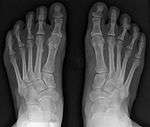

Syndesmosis procedure addresses specifically the two fundamental problems of metatarsus primus varus deformity that gives rise to the bunion deformity. They are leaning and instability of the first metatarsal bone . Syndesmosis procedure uprights the leaning first metatarsal bone with strong binding sutures between it and the second metatarsal bone (Fig. 2) and then also stabilizes it uniquely by creating a fibrous connecting bridge between these two bones (Fig. 3,4). First metatarsal bone can be readily realigned is because by definition of the metatarsus primus varus deformity its first metatarsal is abnormally loose and mobile.